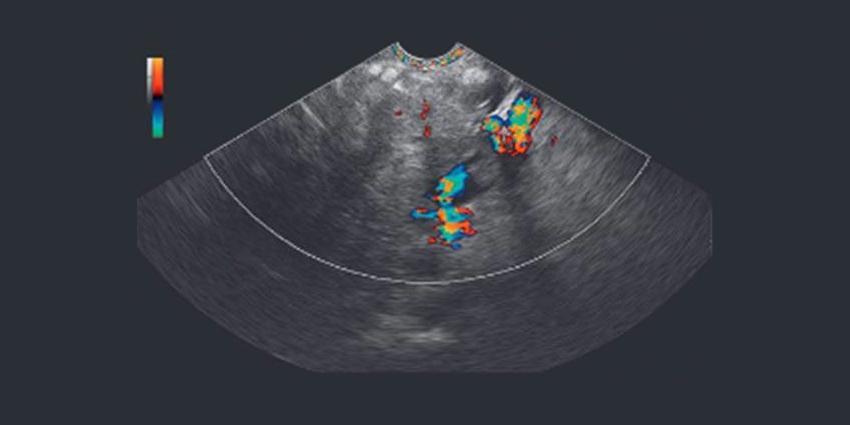

Современный УЗ-эндоскоп EG-3270UK гарантирует высокую точность тонкоигольной аспирации, а также высокое качество изображения. Сочетание этих двух возможностей выводит медицину на новый уровень, давая врачам возможность выполнять широкий спектр процедур.

Ученые с Канады говорят, что этот аппарат можно также использовать для обнаружения рака легких. При этом его возможности намного шире, нежели у остальных устройств, ведь благодаря данному аппарату можно сразу же оценить структуру, степень распространения и другие характеристики недоброкачественного образования. Качество получаемых изображений позволяет быть уверенным в точности диагноза на все 100 процентов.